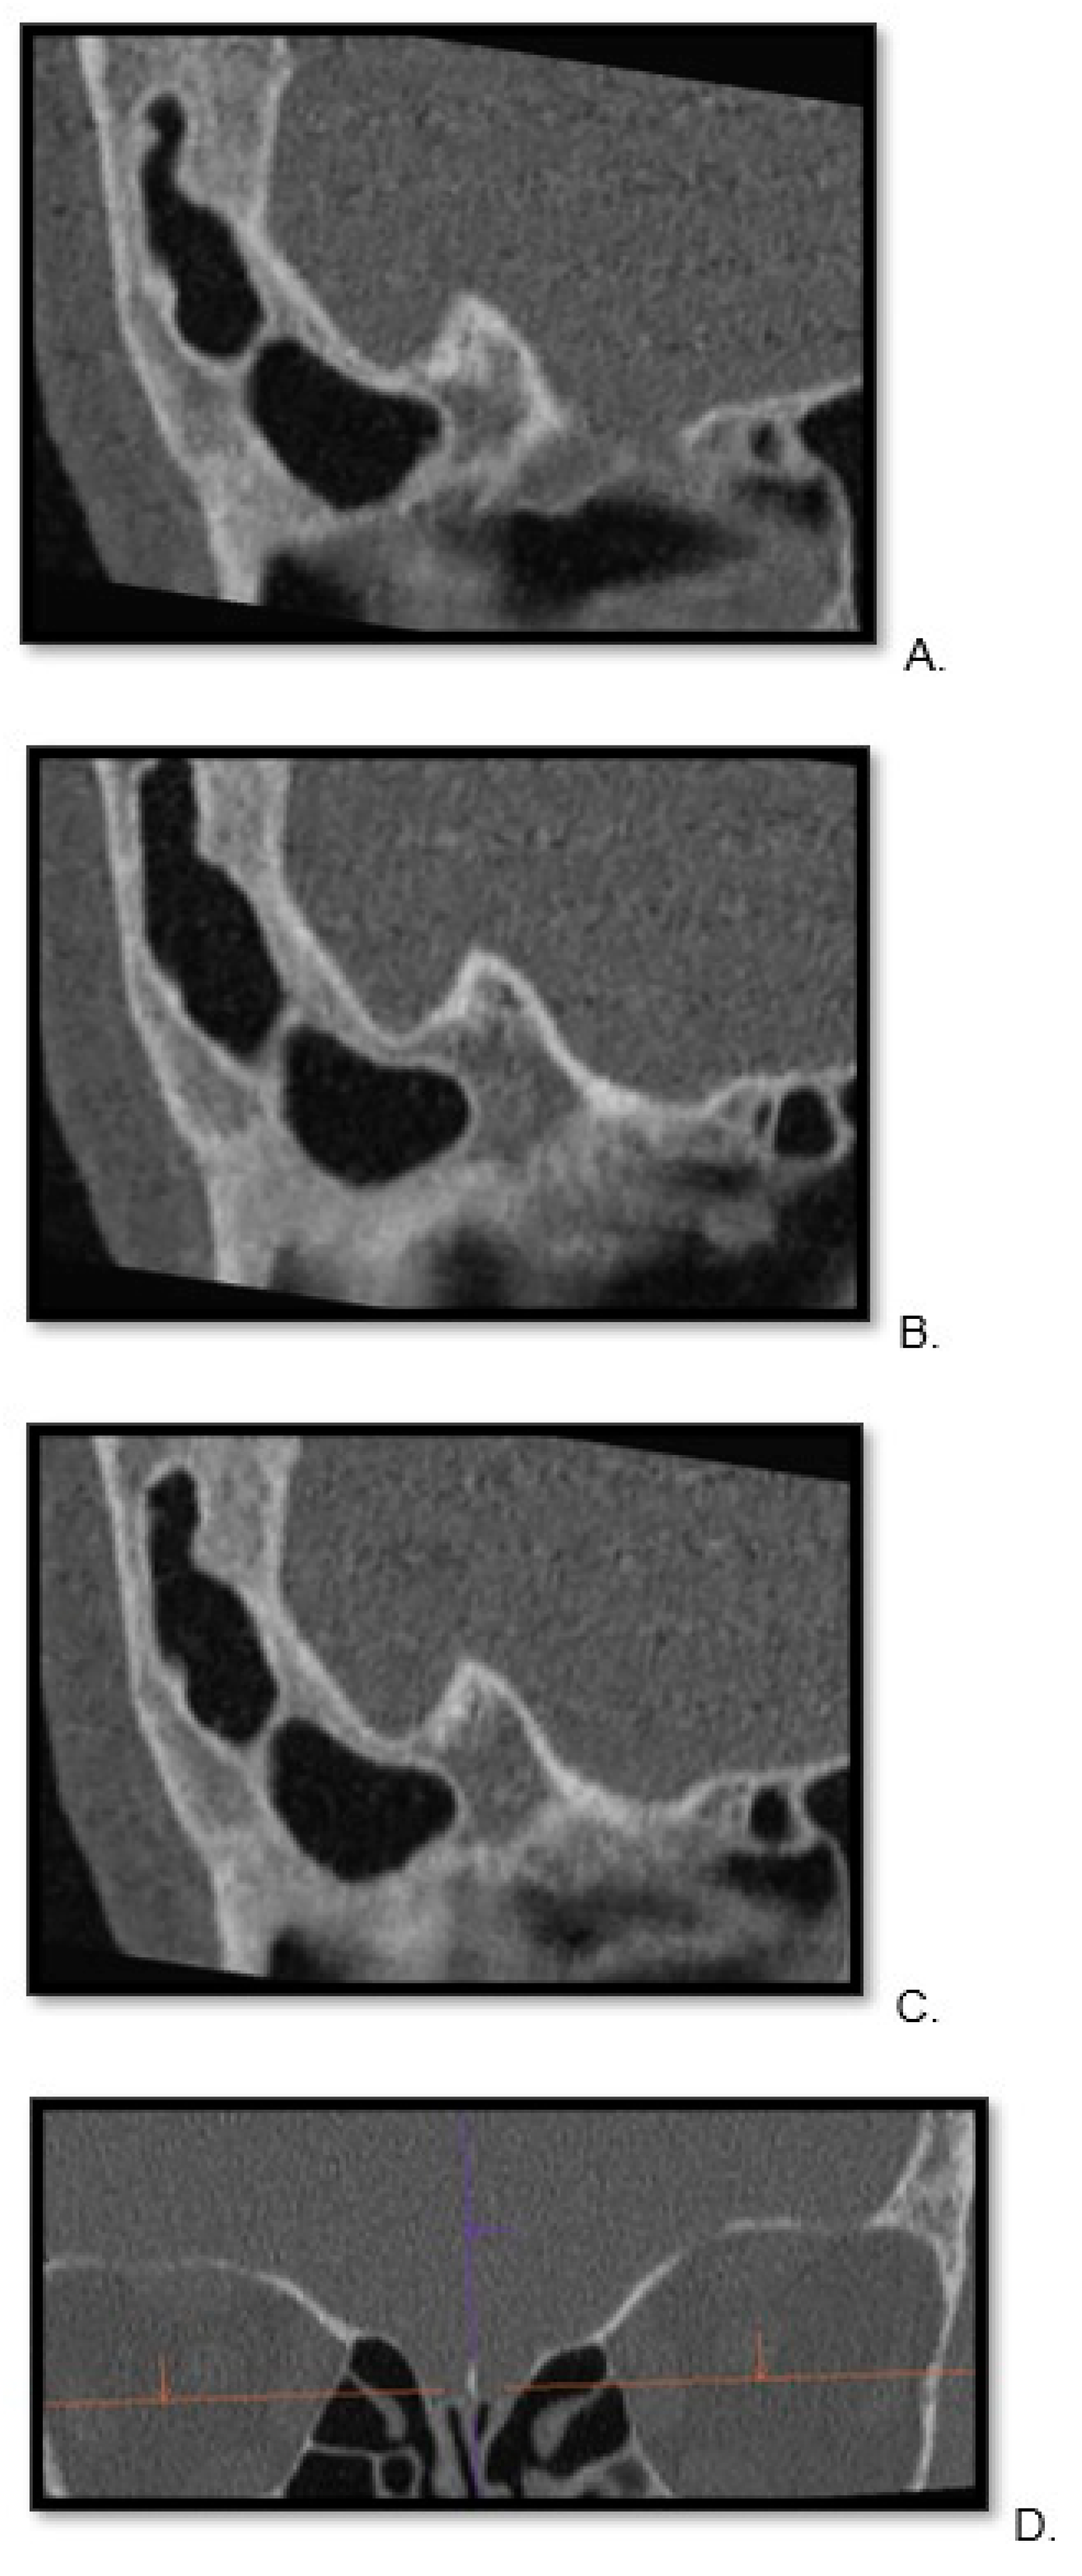

2.3. Image Preparation—Multiplanar Reconstructions

2.6. Evaluation of Qualitative Parameters